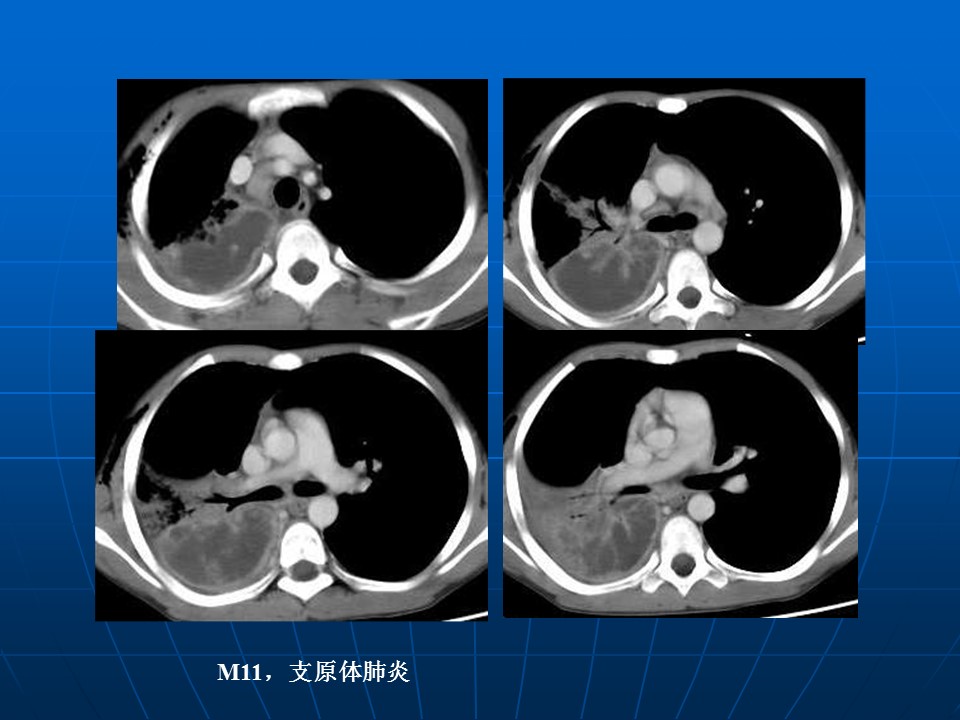

【PPT】肺部炎症新认识点滴